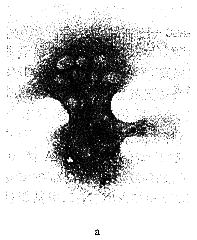

2.2 TRAP染色光镜观察 破骨细胞形态各异,酶活性部位呈红色颗粒样沉淀,分布于全部或大部分胞浆,细胞核呈阴性,同片的其他细胞不着色(图1a),对照组不显色。

图1 a.TRAP染色 分离培养的大鼠OC呈哑铃形,细胞浆呈红色,细胞核阴性 200×; b.TrATPase 染色 分离培养的大鼠OC呈漏斗形,细胞浆呈棕褐色颗粒状,细胞核阴性 200×